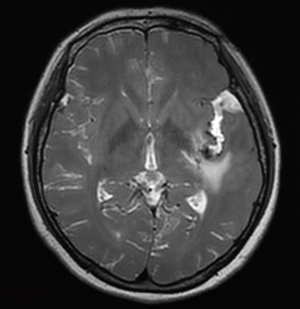

Detailed method

Preoperative CT three-dimensional angiography was performed, and the relevant original images were transferred to the Stealth Station. The three-dimensional images of the patient's skull, cerebral cortex, aneurysm, and other anatomical structures were then reconstructed, and the neurosurgeon designed the surgical plan based on the three-dimensional angiography. At the same time, the position was placed according to the lesion site during the operation. The incisions, bone flap ranges, and surgical paths were designed based on the location of the aneurysm shown by neuronavigation. The aneurysms were clipped intraoperatively under the guidance of neuronavigation. The fluorescence contrast confirmed that the aneurysm was not visible, and the surgery was concluded (Figures 1,2).